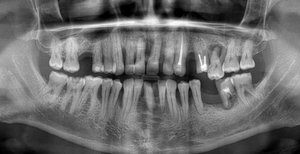

Здравствуйте! Хотелось бы получить общую консультацию по снимку. Очень плохие зубы с детства, постоянно беспокоят и просто разрушаются. Хотелось бы понять — есть возможность спасти хотя бы корни большинства зубов? Существуют ли вообще очень серьезные проблемы?

Добрый день. Особых проблем я не вижу, уважаемый пациент. 4.7 зуб необходимо тщательно осмотреть на предмет пригодных тканей для последующего восстановления вкладкой и коронкой, на 4.6 также есть воспаление на верхушке корня, все также необходимо пролечить затем изготовить культевую вкладку и коронку, 3.6 необходимо перелечить, плохая некачественная пломбировка, а также большая по площади пломба, при неблагоприятном исходе может привести к сколу стенки, что в последствии также к потере зуба, 2.6 скорее всего удалится, но еще раз стоит сделать ревизию, 1.6 необходимо перелечить.